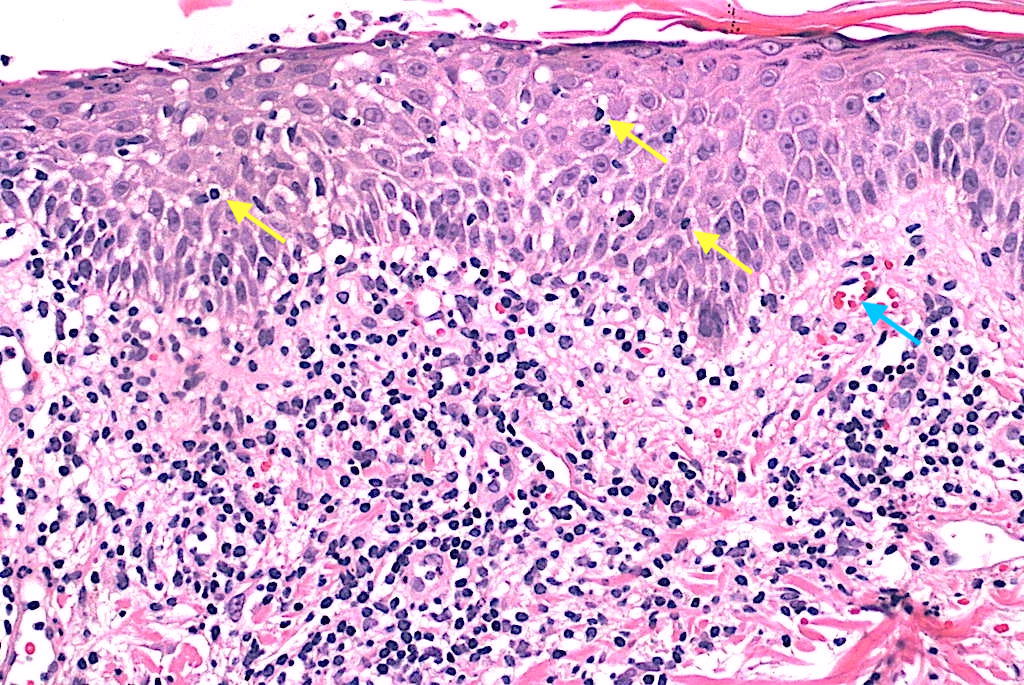

Biopsia punch 4–5 mm de lesión temprana ± costrosa con H&E; considerar segunda biopsia perilesional para IFD si dudas de vasculitis. Muhlbauer 1984.

Inmuno: panel T (CD3, CD4, CD8, CD30); TCR-γ/β si persiste duda con LyP/MF (papulosis linfomatoide/micosis fungoides). Wood 1987, Dereure 2000.